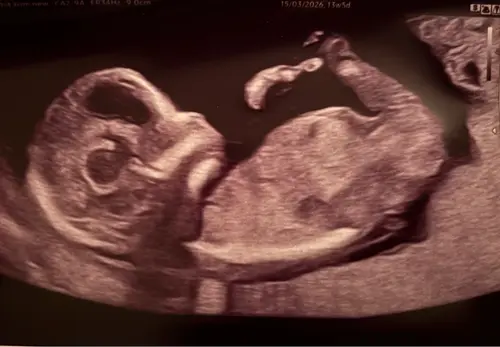

Wat denken jullie meisje of jongen?

We zullen het pas zeker weten bij de geboorte, maar mijn schoonzusje hield zich bezig met de theorieën en nu ben ik wel benieuwd wat anderen denken

Ik weet niet goed of de nub hier te zien is…

Ik zelf zie hem ook niet echt maar ook te weinig verstand van ik zal nog eens een andere erbij zetten van dezelfde echo

Oeh lastig, ik zie wel een nub maar vind het lastig om te zien of deze nu meer in een driehoek staat tov de ruggengraat of dat het recht door loopt 😅. Misschien zijn er kenners die het zien?